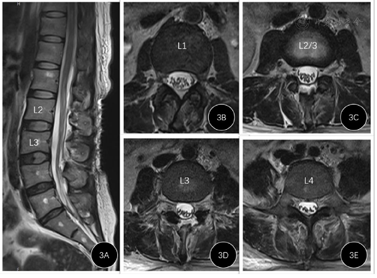

术后第1天患者腰痛缓解,鞍区麻木感仍存在。术后第2天椎旁引流管共引流10 ml淡血性液体,予拔除。术后第3天患者觉鞍区麻木感缓解,肌力稍有恢复。腰大池引流管每日引流约200 ml脑脊液,脑脊液逐渐由血性转为淡黄色,术后1周拔除腰大池引流管,患者肌力恢复至Ⅳ级,可解大便,但拔除导尿管后不能排尿,遂再次留置导尿管。复查腰椎磁共振可见血肿少量残余,蛛网膜下腔空间恢复(图3)。至术后14 d,予患者手术切口拆线,切口愈合良好。再次拔除导尿管,顺利排尿。患者肌力、二便功能正常,恢复日常生活。术后半年电话随访患者,未再出现腰痛、下肢无力、二便障碍症状。